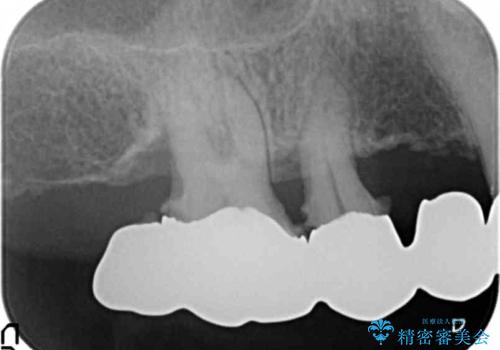

保存可能な2本の歯を用いて、マグネットデンチャー(磁性アタッチメントを用いた入れ歯)による治療を行いました。

- ¥780,000 (根管治療×2本、土台×2本、磁性アタッチメント×2、金属床義歯)費用は治療当時の料金となります